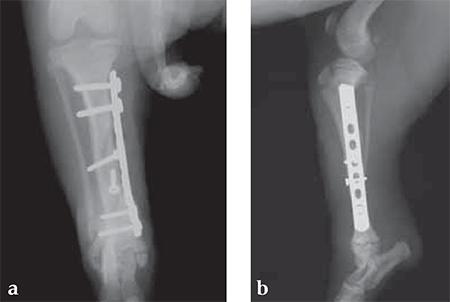

A 12-week-old Yorkshire Terrier, 1.3 kg

(Case provided by Alessandro Piras, Banbridge, Northern Ireland)

Small Bones, Small Plates: Clinical Application of Mini LCP